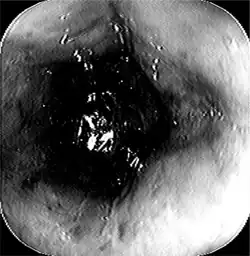

Acute esophageal necrosis-endoscopic view demonstrated progressive dusky and discolored esophageal mucosa.